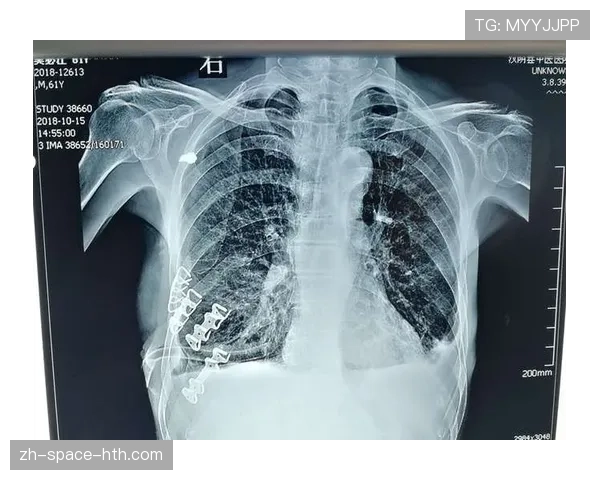

弗鲁姆在事故中遭受的多处严重伤害给他的身体带来了巨大挑战。肋骨骨折和腰椎骨折使他难以进行日常活动,而气胸和心包破裂则对他的呼吸系统造成了直接威胁。医疗团队在第一时间对他进行了全面检查,并制定了详细的治疗方案,以确保他的生命安全。经过数周的治疗和观察,弗鲁姆的病情逐渐稳定,但恢复过程仍然漫长而艰辛。